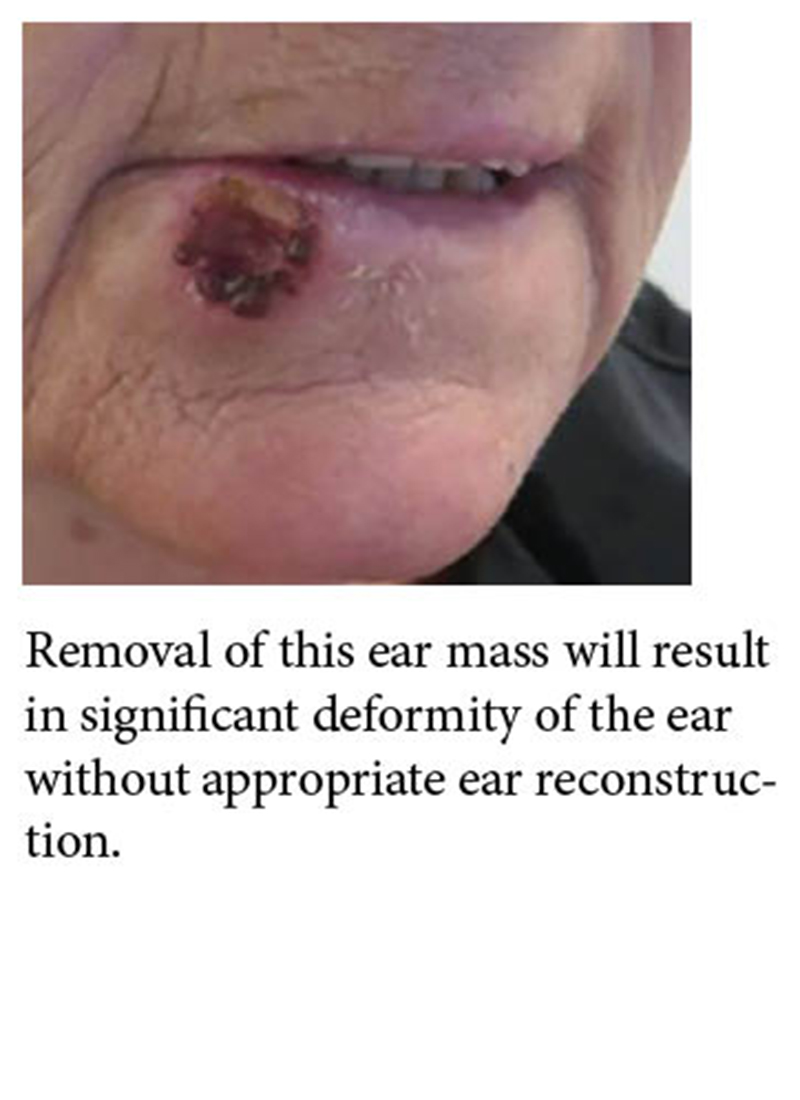

Facial Masses and Scarring

Benign and malignant tumors can arise anywhere on the face or ears.

Mass removal can result in significant facial disfigurement if not reconstructed appropriately immediately after removal.

Issues can arise years later from unexpected consequences of the initial reconstructions.

Unsightly scars can be revised at any time by facial reconstruction.